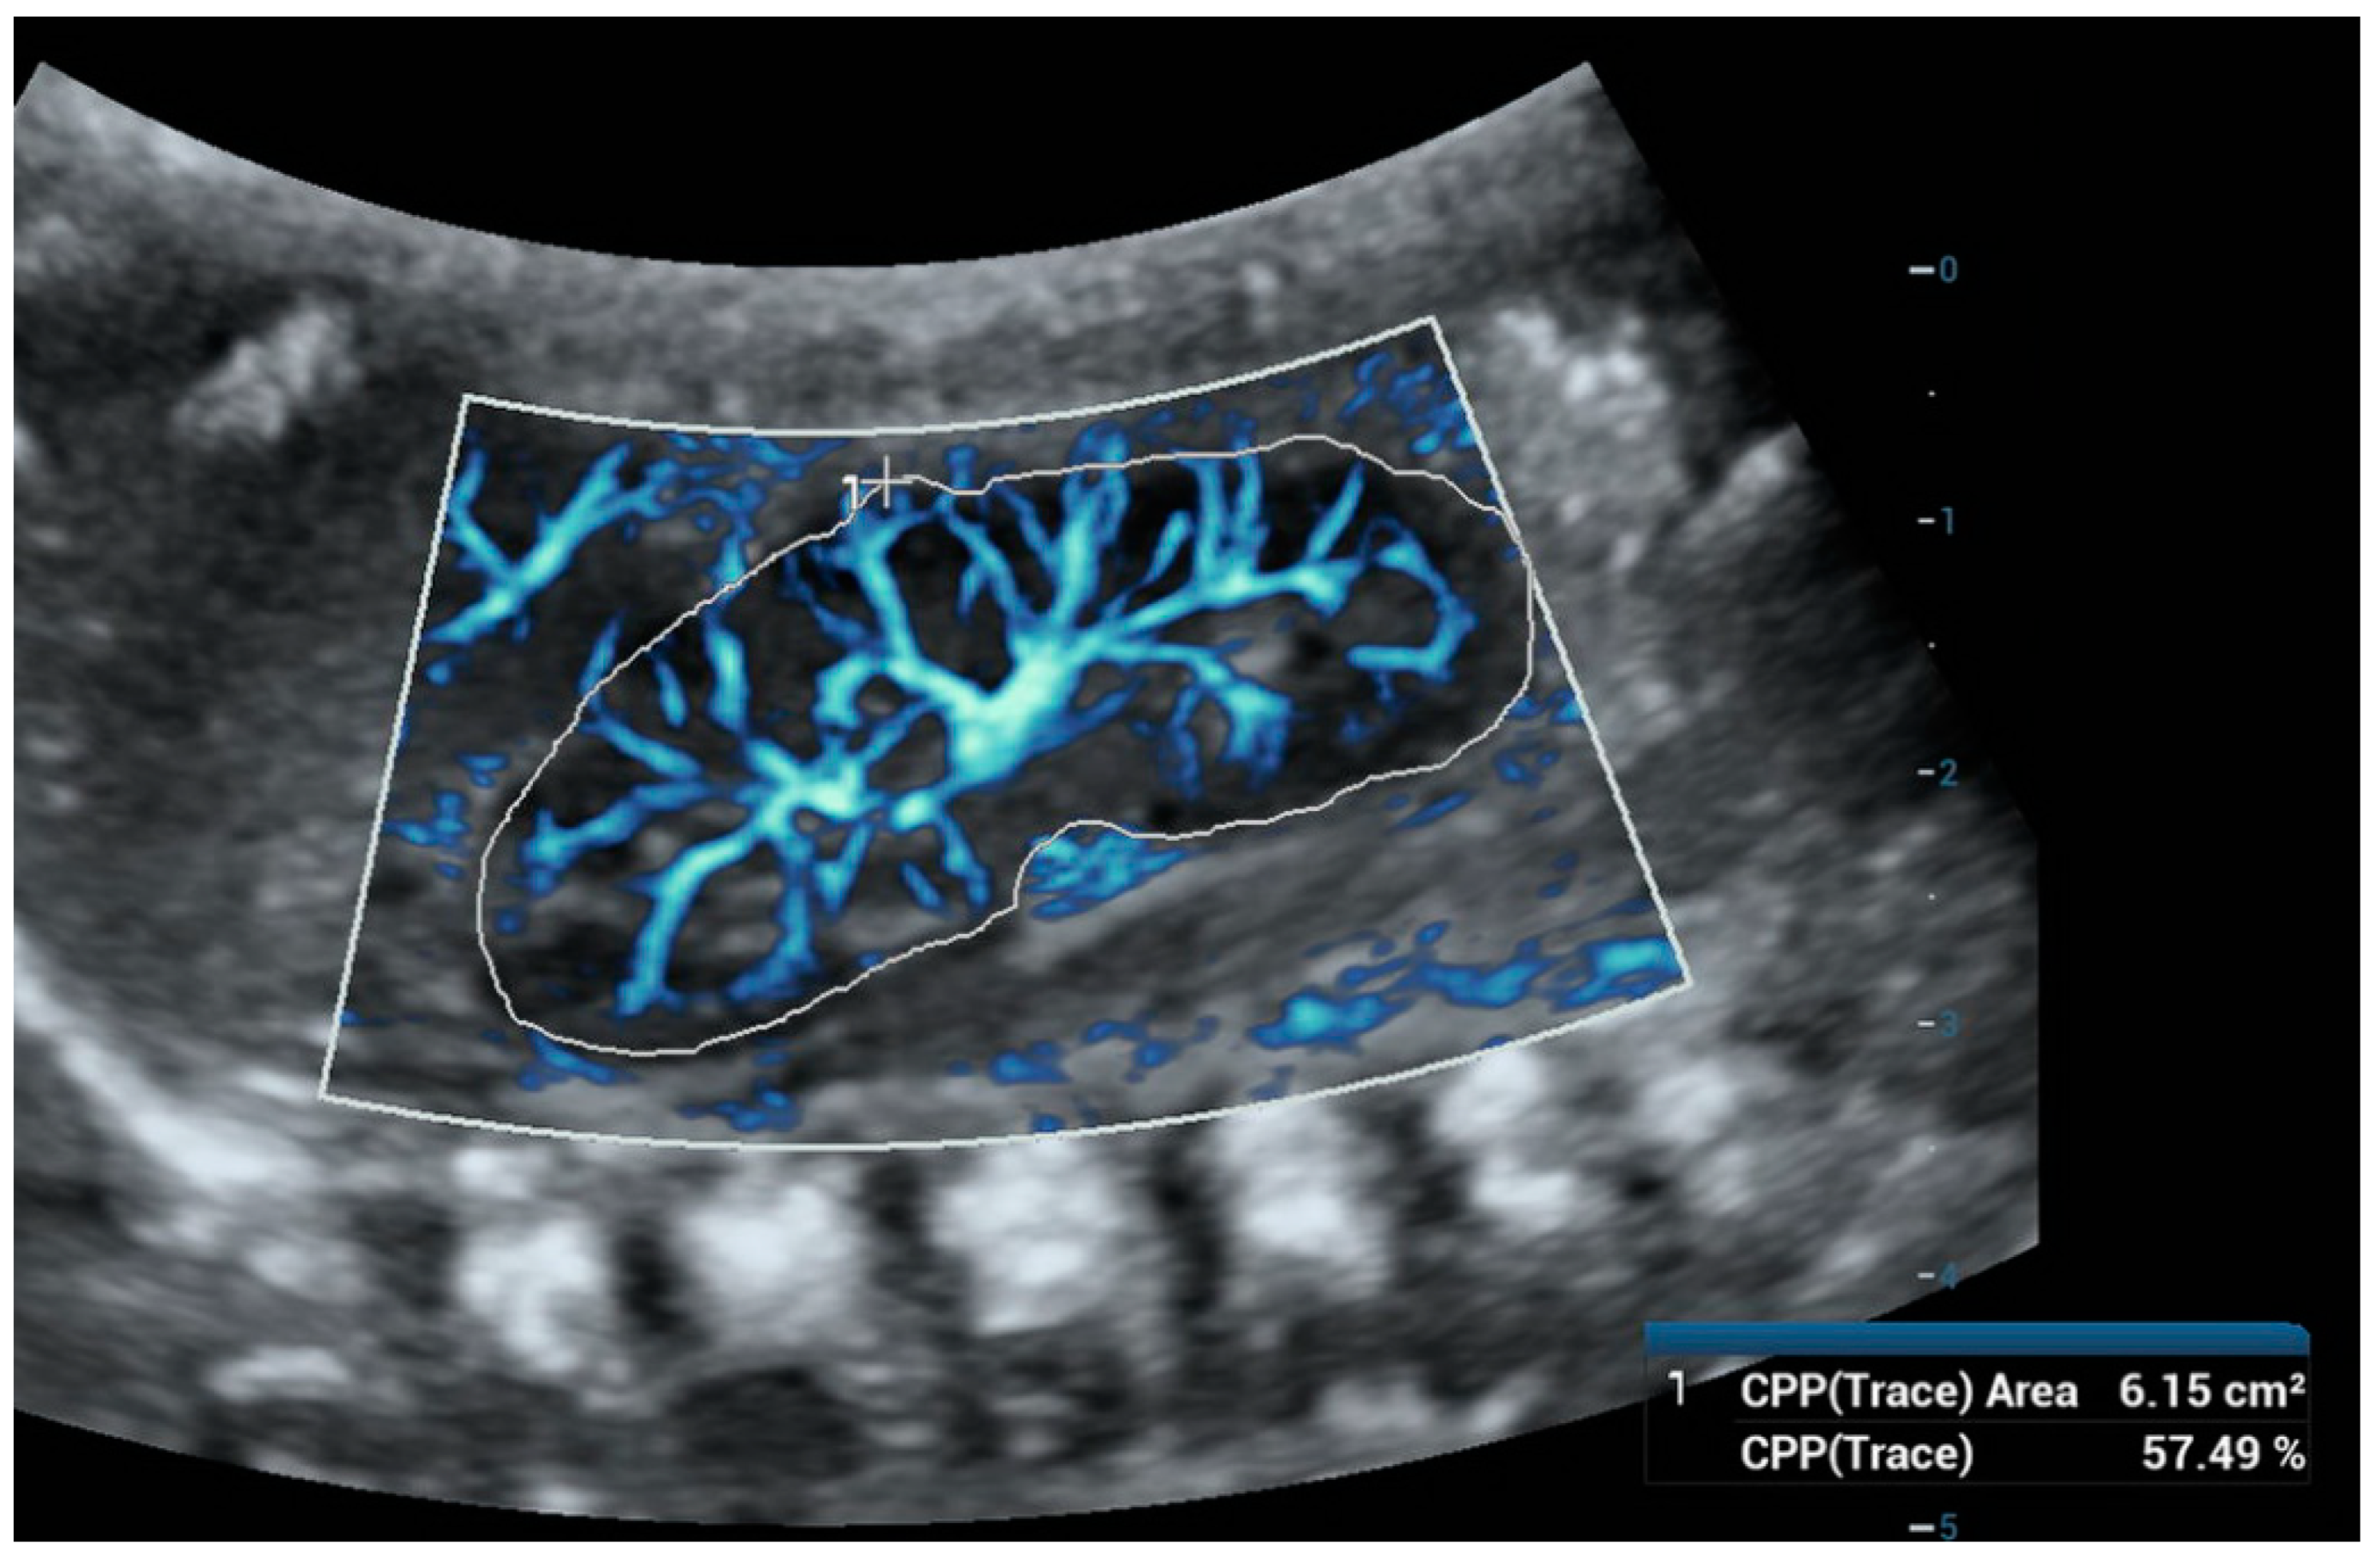

6. Ultra-Microangiography (UMA)

- Aziz, M.U.; Eisenbrey, J.R.; Deganello, A.; Zahid, M.; Sharbidre, K.; Sidhu, P.; Robbin, M.L. Microvascular Flow Imaging: A State-of-the-Art Review of Clinical Use and Promise. Radiology 2022, 305, 250–264. [Google Scholar] [CrossRef] [PubMed]

- Chen, M.; Fu, X.; Shen, Y. Evaluation of Multimode Color Doppler Flow Imaging in the Diagnosis of Solid Renal Tumor. Contrast Media Mol. Imaging 2021, 2021, 656877. [Google Scholar] [CrossRef]

- Albaladejo-Fuertes, S.; Jung, E.M.; Büchler, C.; Gülow, K.; Kandulski, A.; Kempa, S.; Müller, M.; Tews, H.C. High-Resolution Visualization of Intestinal Microcirculation Using Ultra-Microangiography in Patients with Inflammatory Bowel Disease: A Pilot Study. J. Gastrointest. Liver Dis. 2024, 33, 194–202. [Google Scholar] [CrossRef]

- Zhao, C.; Wang, Q.; Wang, M.; Tao, X.; Liu, S.; Qi, Z.; Lanxi, X.; Liu, D.; He, X.; Tian, X.; et al. Ultra-Microangiography in Evaluating the Disease Activity of Rheumatoid Arthritis and Enhancing the Efficacy of Ultrasonography: A Preliminary Study. Eur. J. Radiol. 2021, 137, 109567. [Google Scholar] [CrossRef]

- Armaly, Z.; Abu-Rahme, M.; Kinaneh, S.; Hijazi, B.; Habbasshi, N.; Artul, S. An Innovative Ultrasound Technique for Early Detection of Kidney Dysfunction: Superb Microvascular Imaging as a Reference Standard. J. Clin. Med. 2022, 11, 925. [Google Scholar] [CrossRef] [PubMed]